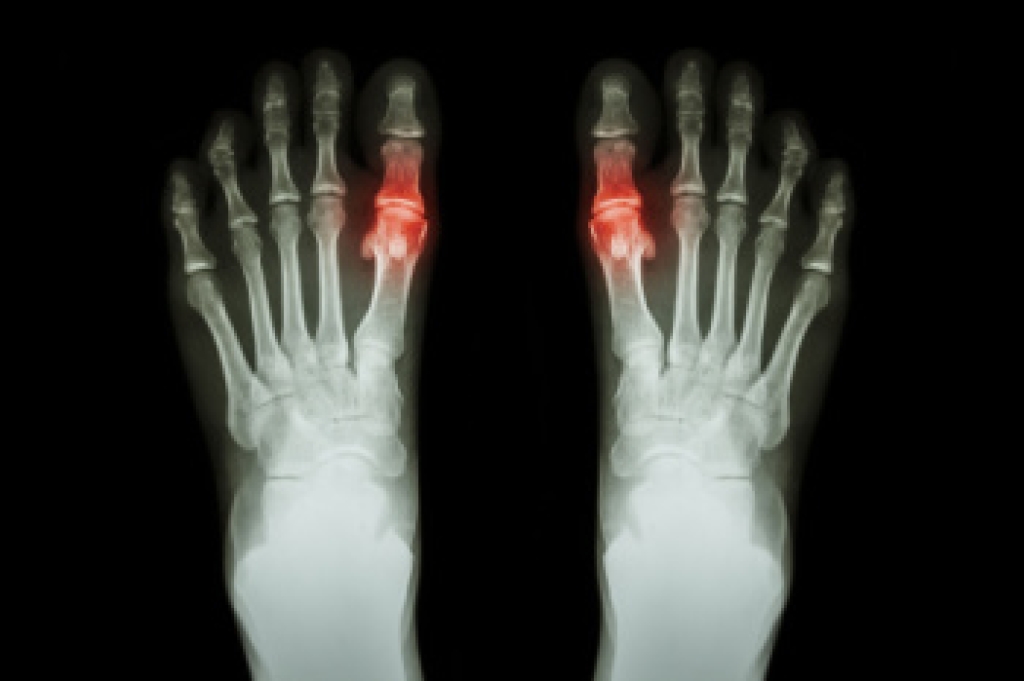

Podiatrists often perform two tests – blood tests and x-rays – when trying to diagnose bunions, especially in the early stages of development. Blood tests help determine if the foot pain is being caused by something else, such as arthritis, while x-rays provide a clear picture of your bone structure to your provider.